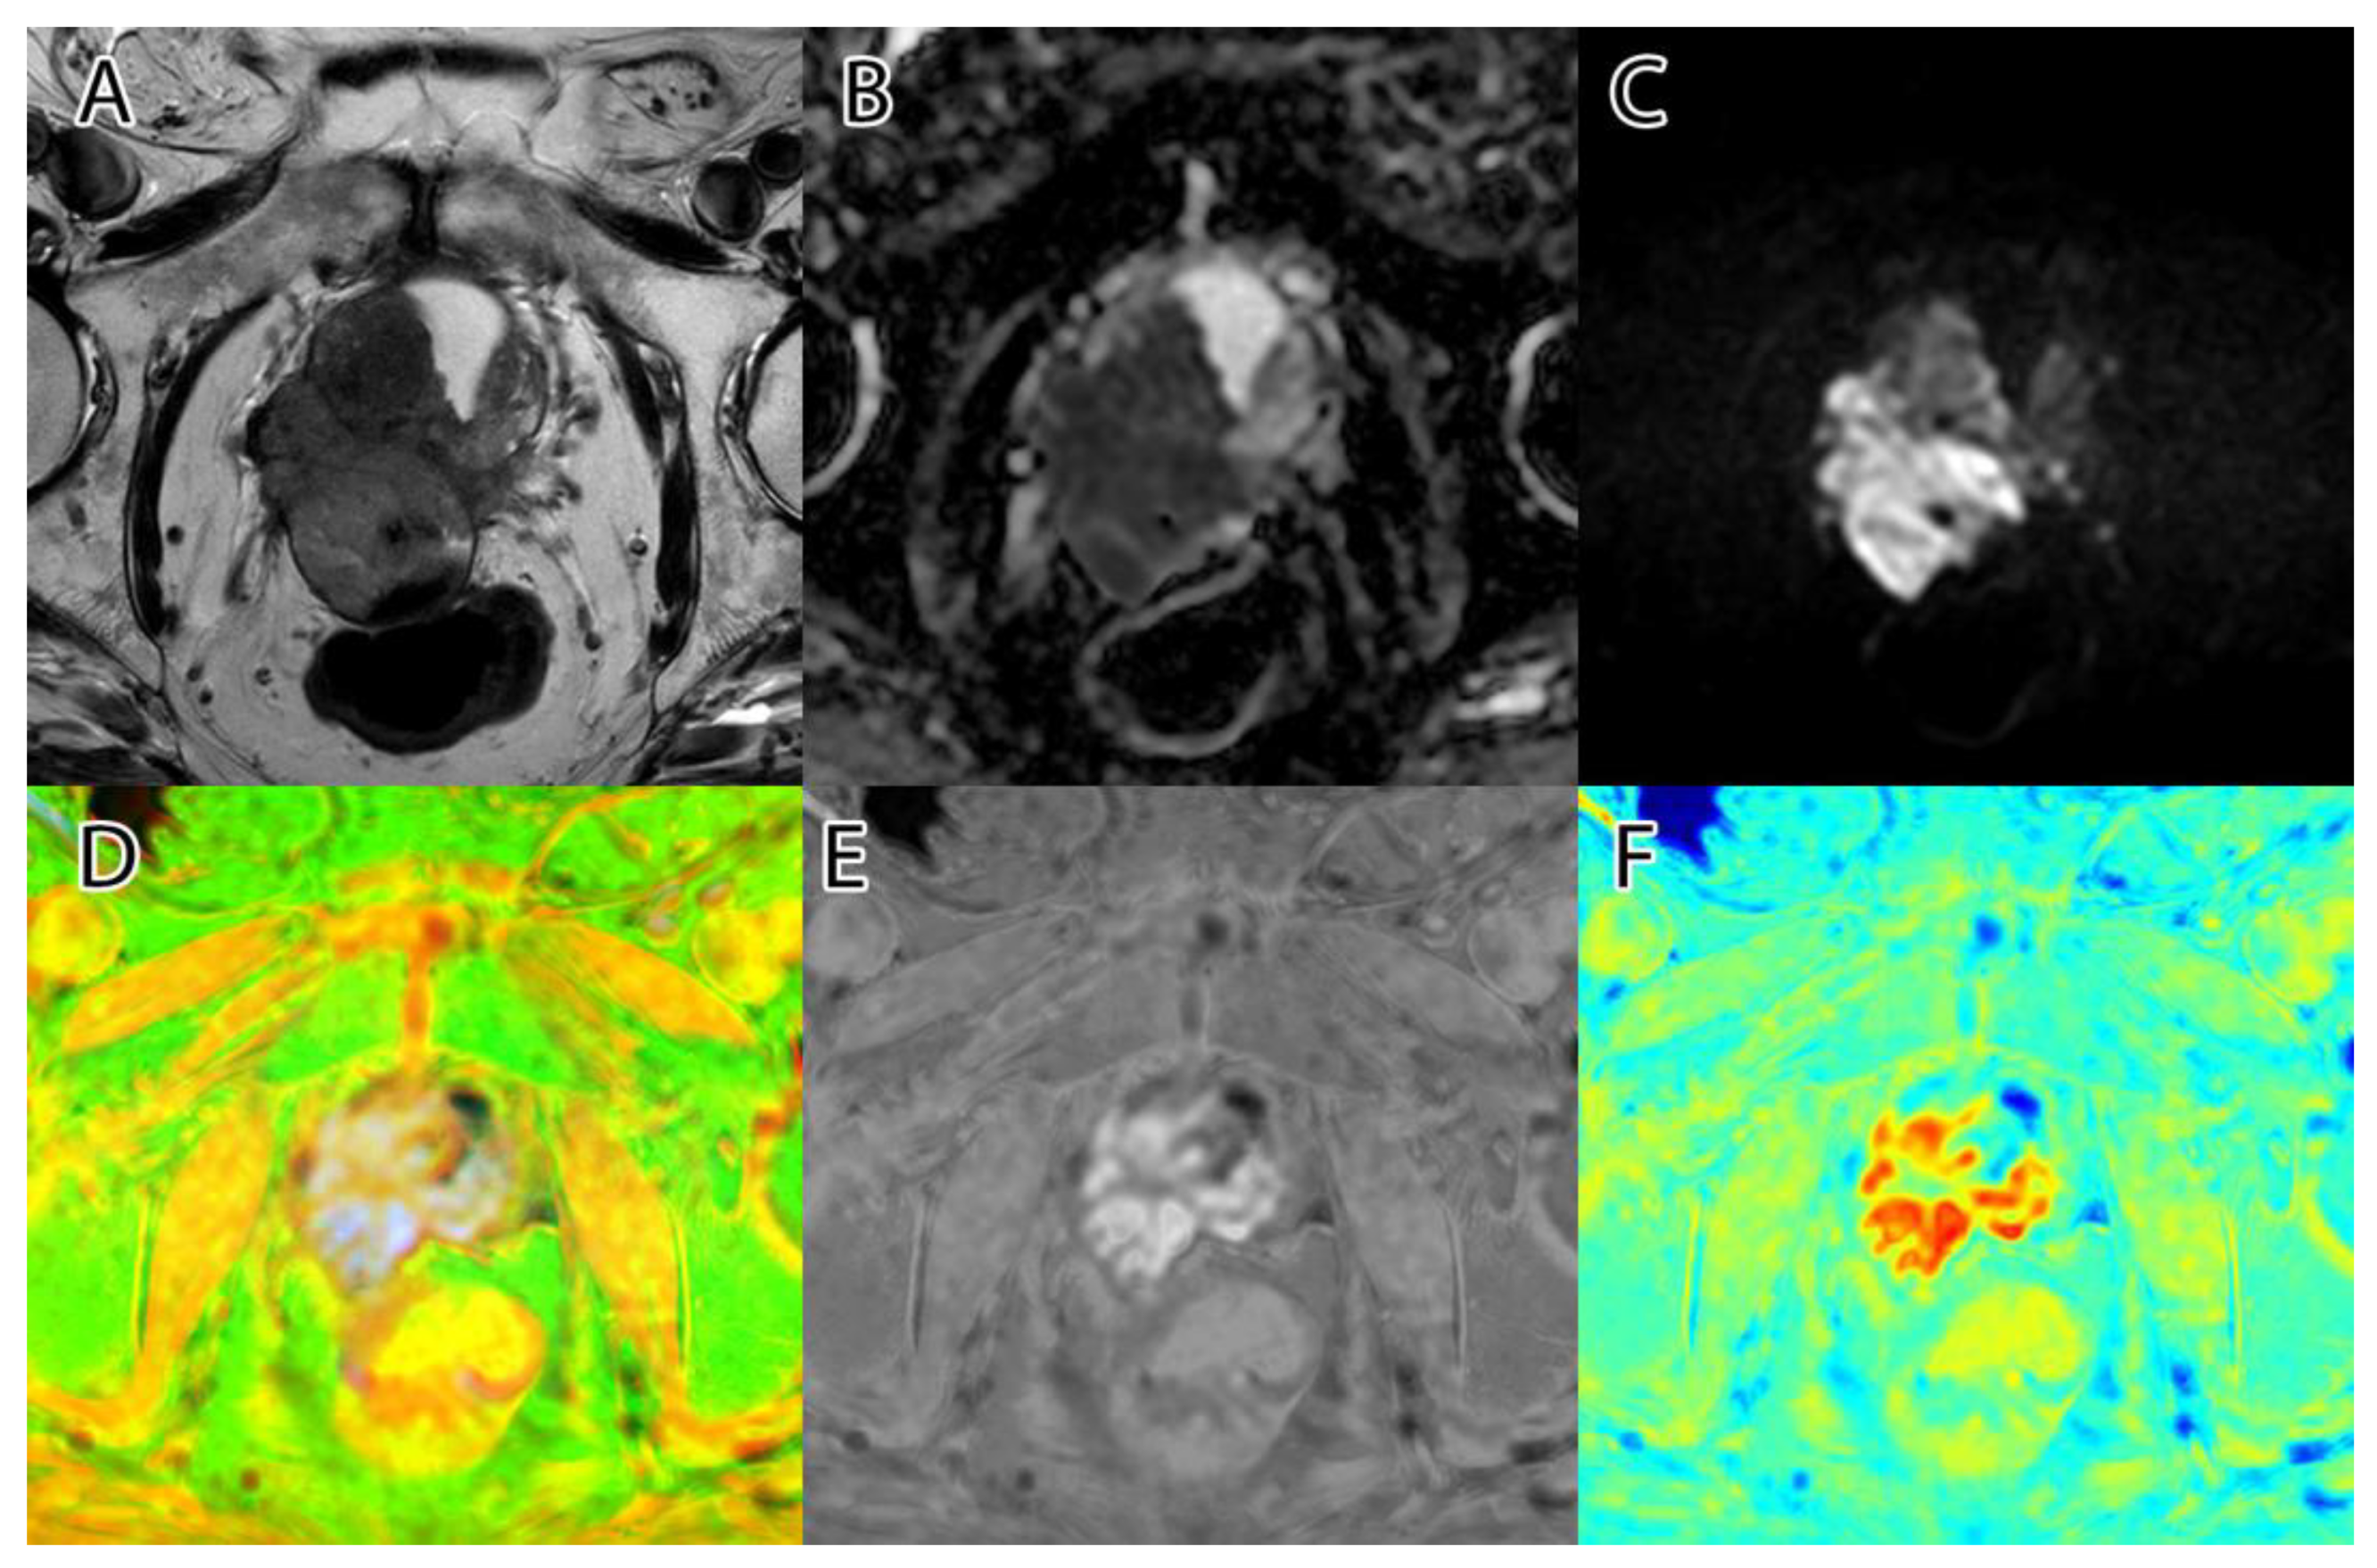

The sixth and final step was to compute the final intensity mask by subtracting the square root from the square sum of the alpha–beta channels and subtracting the resulting value from the luminance. The resulting intensity image can be seen in Figure 2B and Figure 3B. By adding the ‘jet’ color map to it, we obtained a colored intensity map that highlights the tumoral areas, as seen in Figure 2C and Figure 3C.

Figure 3. PI-RADS 5 patient: (A)—T2WI; (B)—ADC; (C)—DWI; (D)—RGB fused image; (E)—grayscale tumor intensity image; (F)—‘jet’-mapped tumor intensity image.

Samples of the computed tumor intensity images can be seen in Figure 2 for a PI-RADS 2 patient and in Figure 3 for a PI-RADS 5 patient. Notice the difference in “jet” intensity between the control patient and the patient with extraprostatic invasion.